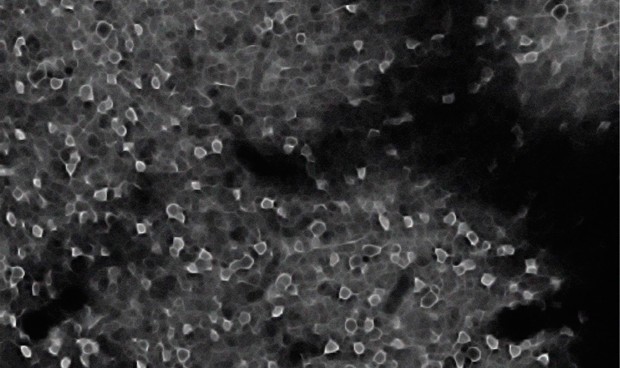

El equipo de la investigación, publicada este jueves en la revista 'Cell', detectó simultáneamente más de 500 neuronas en seis regiones del cerebro en ratones. Los datos resultantes de más de 45.000 grabaciones les permitieron comparar cómo se procesa la información relacionada con el valor en cada área del cerebro. Este vasto conjunto de datos les llevó a la RSC, un área en la capa externa del cerebro conocida como la corteza, que conecta una variedad de redes y funciones cerebrales.